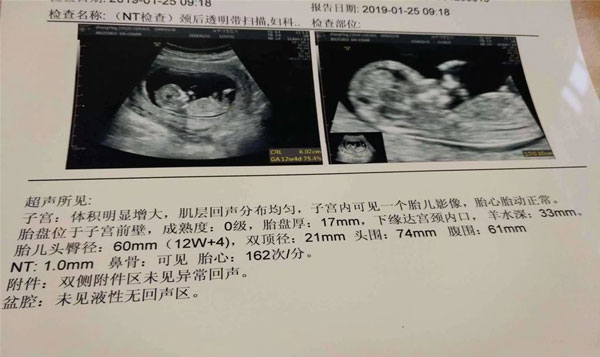

nt单子男孩有圈圈是真是假?怀孕之后,对于胎儿性别的猜想,前有前辈各种小秘诀,后又如今网友通过孕检的各种数据分辨男女,最近流传出了一个分辨胎儿男女的方法,就是看nt单子上的图案,上面有圈圈的就是男孩,这个方法看胎儿的男女是真是假,我们来听听相关孕妈的意见。

nt单子男孩有圈圈这个辨别方法是没有任何的科学依据的。据了解很多人所说的圈圈位置是指男女生殖器的位置,通过生殖器的特点辨别胎儿的男女不失为一种有效的方式,但是医生在截取图像时,每个医生截取的方位都不一样,而且胎儿在肚子里时,和妈妈会有脐带的链接,网友所看到的圈圈图案,难保不是脐带的成像图片。

NT检查其实只是一种检查宝宝颈项透明度的手段,这个检查主要是用来判断宝宝目前发育的情况,从而达到初次排畸的目的,并不能成为确定胎儿男女的依据,如果在nt检查的图像上如果发现有圈圈,很有可能也只是NT检查成像的问题,这点大家需要知晓。